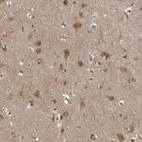

Immunohistochemical staining of human cerebral cortex shows moderate cytoplasmic positivity in neuronal cells.